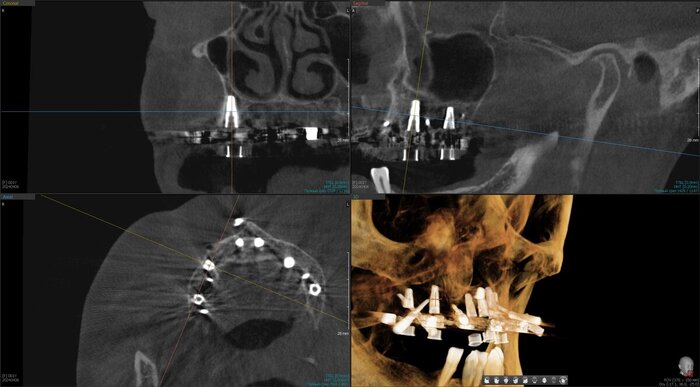

Получилось так, что сверху всего 8 зубов, по 4 с каждой стороны. Чёрная точка (которую вы точно увидите, скос эмали на зубе 1.1) - конструктивные особенности, всё это будет закрыто пломбировочным материалом. Зуб 1.1 - дополнительный имлантат, который потом планируем убрать. Он нужен лишь для усиления, ибо торк полноценный был получен только на одном из остальных 6-ти установленных.

Так же важный момент - верхний протез соприкасается с нижним только в точках полученного торка (их всего 2), остальное "на весу" и жевать не способно.

не играет решающей роли ,сколько дней от имплантации до постановки протеза прошло. Важен торк (усилие) и пассивность конструкции. То есть протез на имплантаты должен усаживаться без боли, пассивно.

И будет успех.